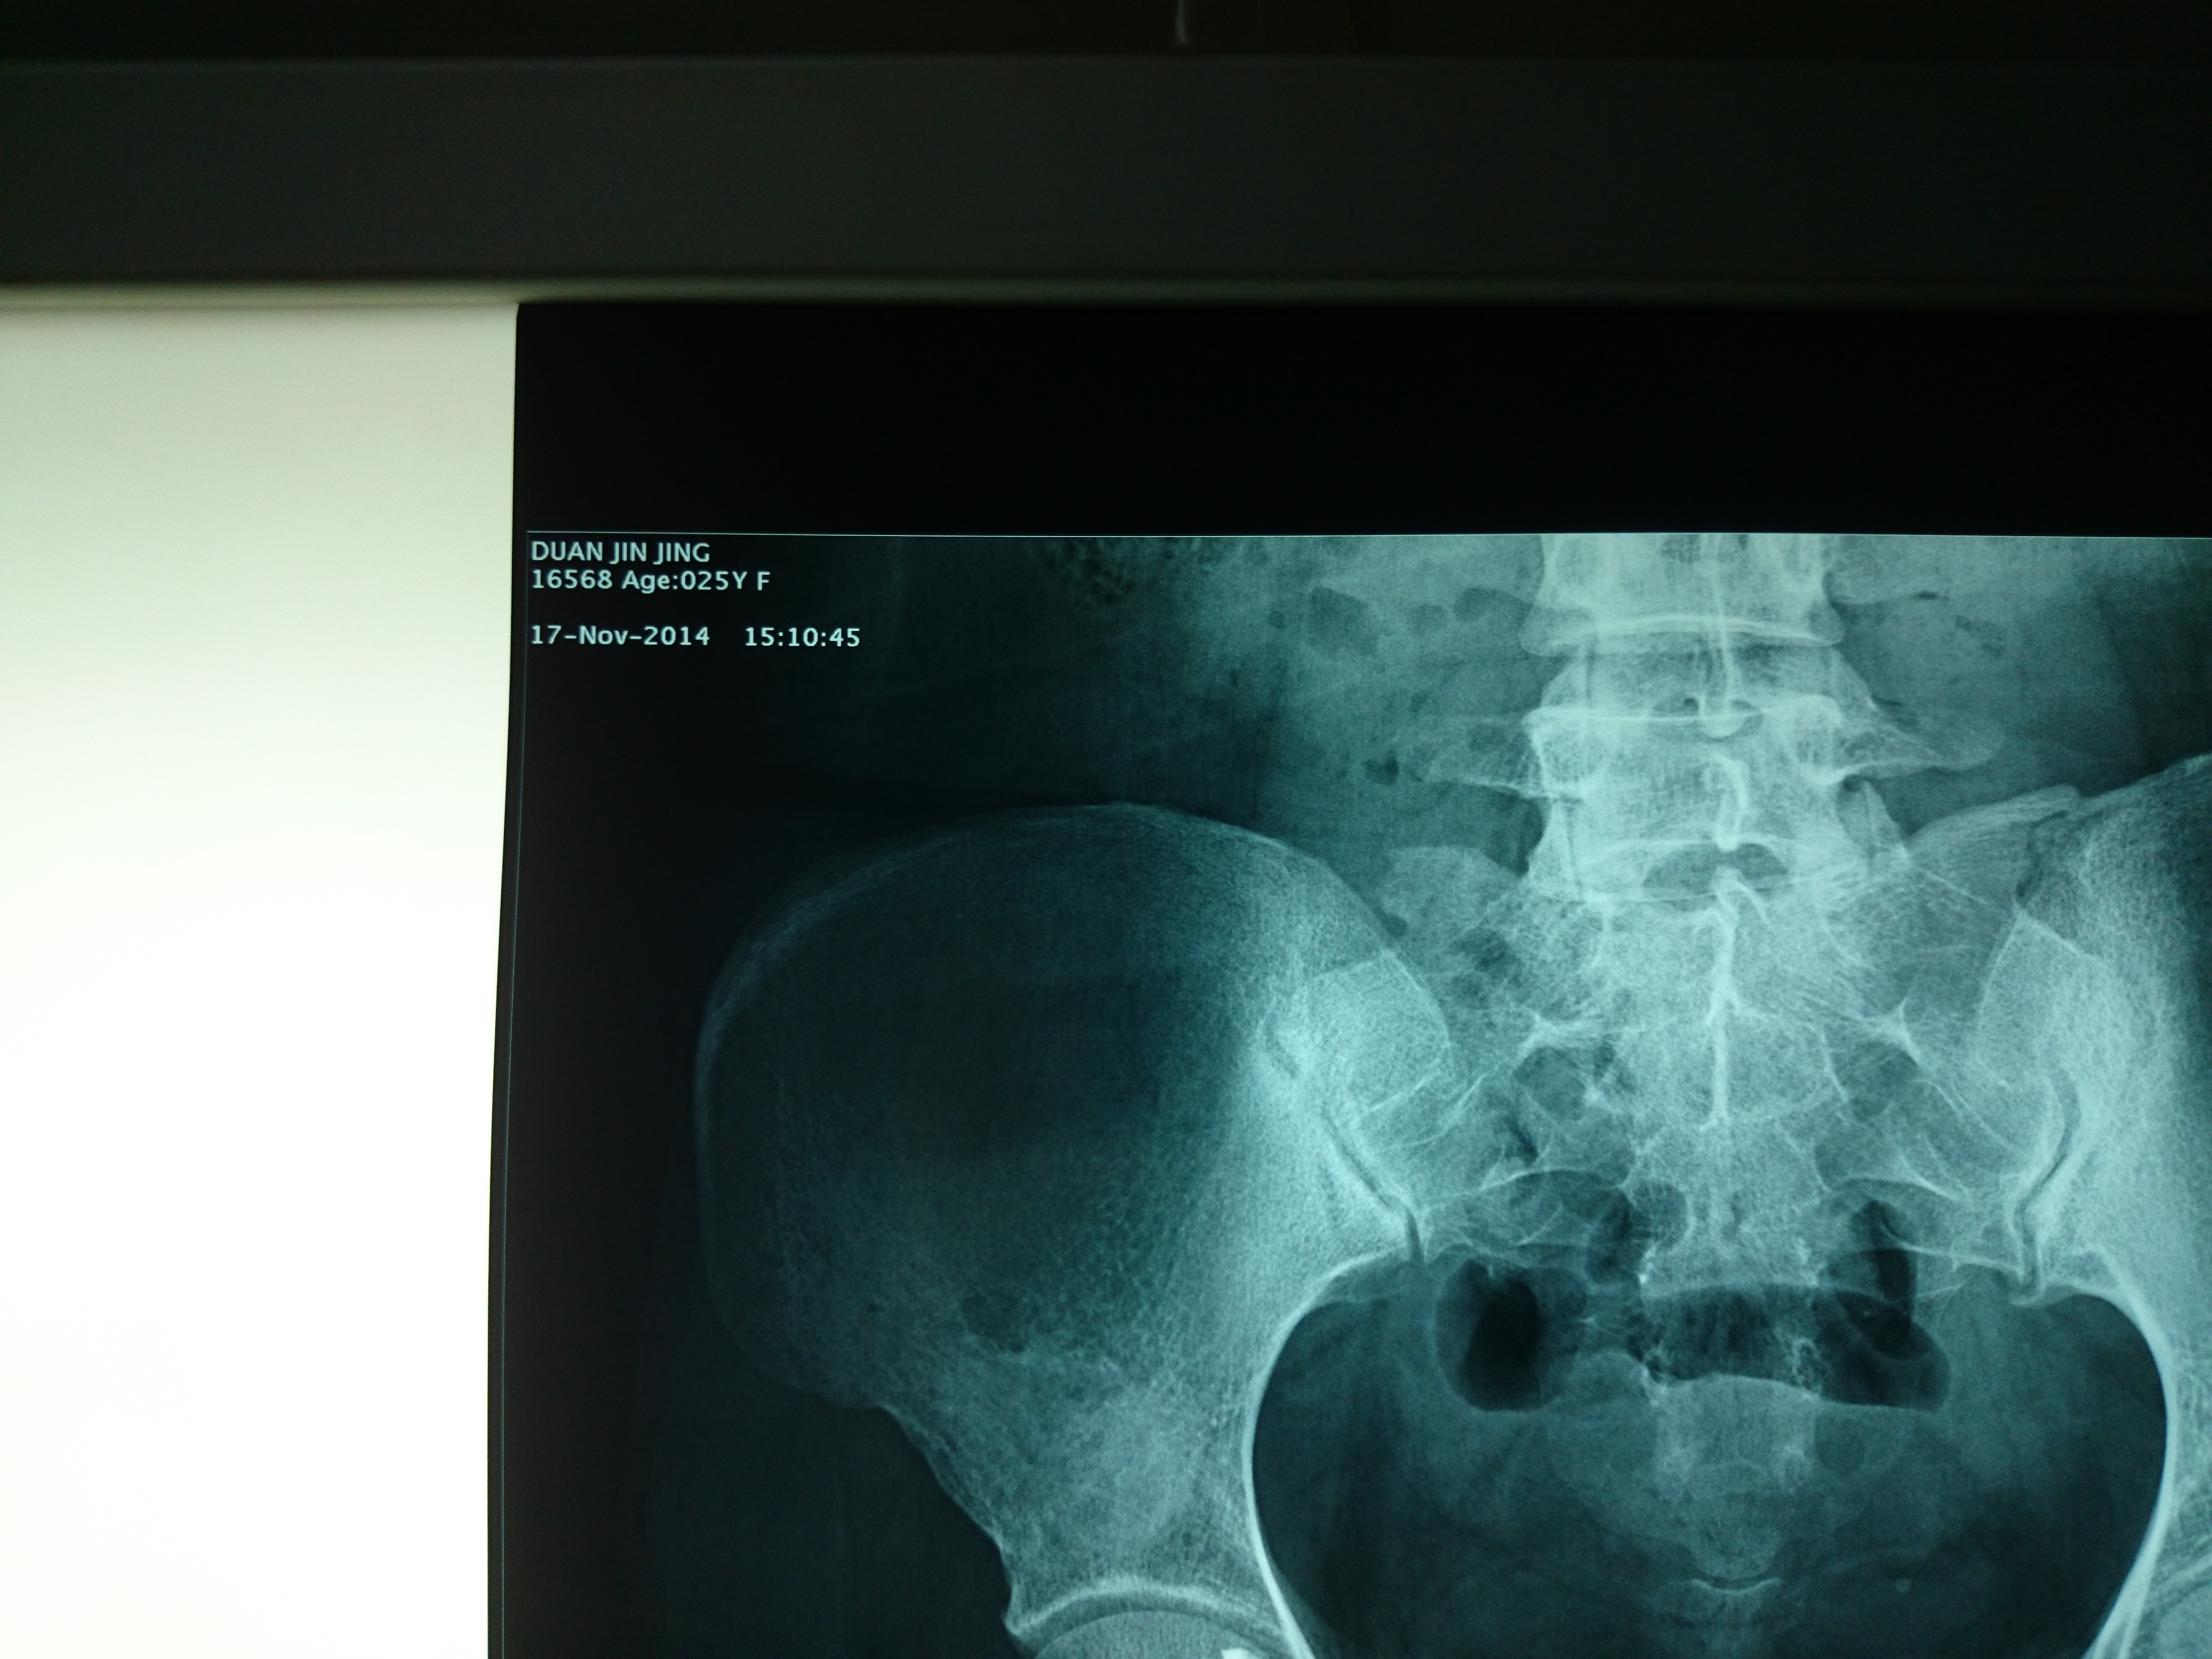

首页 > 张恒云工作室 > 影像资料 十六